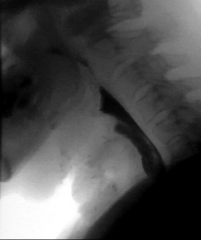

At the onset of the procedure, direct laryngoscopy, esophagoscopy, and retrograde esophagoscopy were performed to identify the location of the fistula and the site and extent of the PES. The TEF was identified immediately distal to the cricoid cartilage and was approximately 4 millimeters in diameter. The proximal and distal esophageal segments both ended in blind pouches with approximately 2 centimeters of complete stenosis between them (Figure 4).

Figure 4 Retrograde esophagoscopy demonstrating a blind pouch at the proximal extent of the distal esophageal segment, consistent with complete esophageal stenosis.

Figure 4: Retrograde esophagoscopy demonstrating a blind pouch at the proximal extent of the distal esophageal segment, consistent with complete esophageal stenosis.